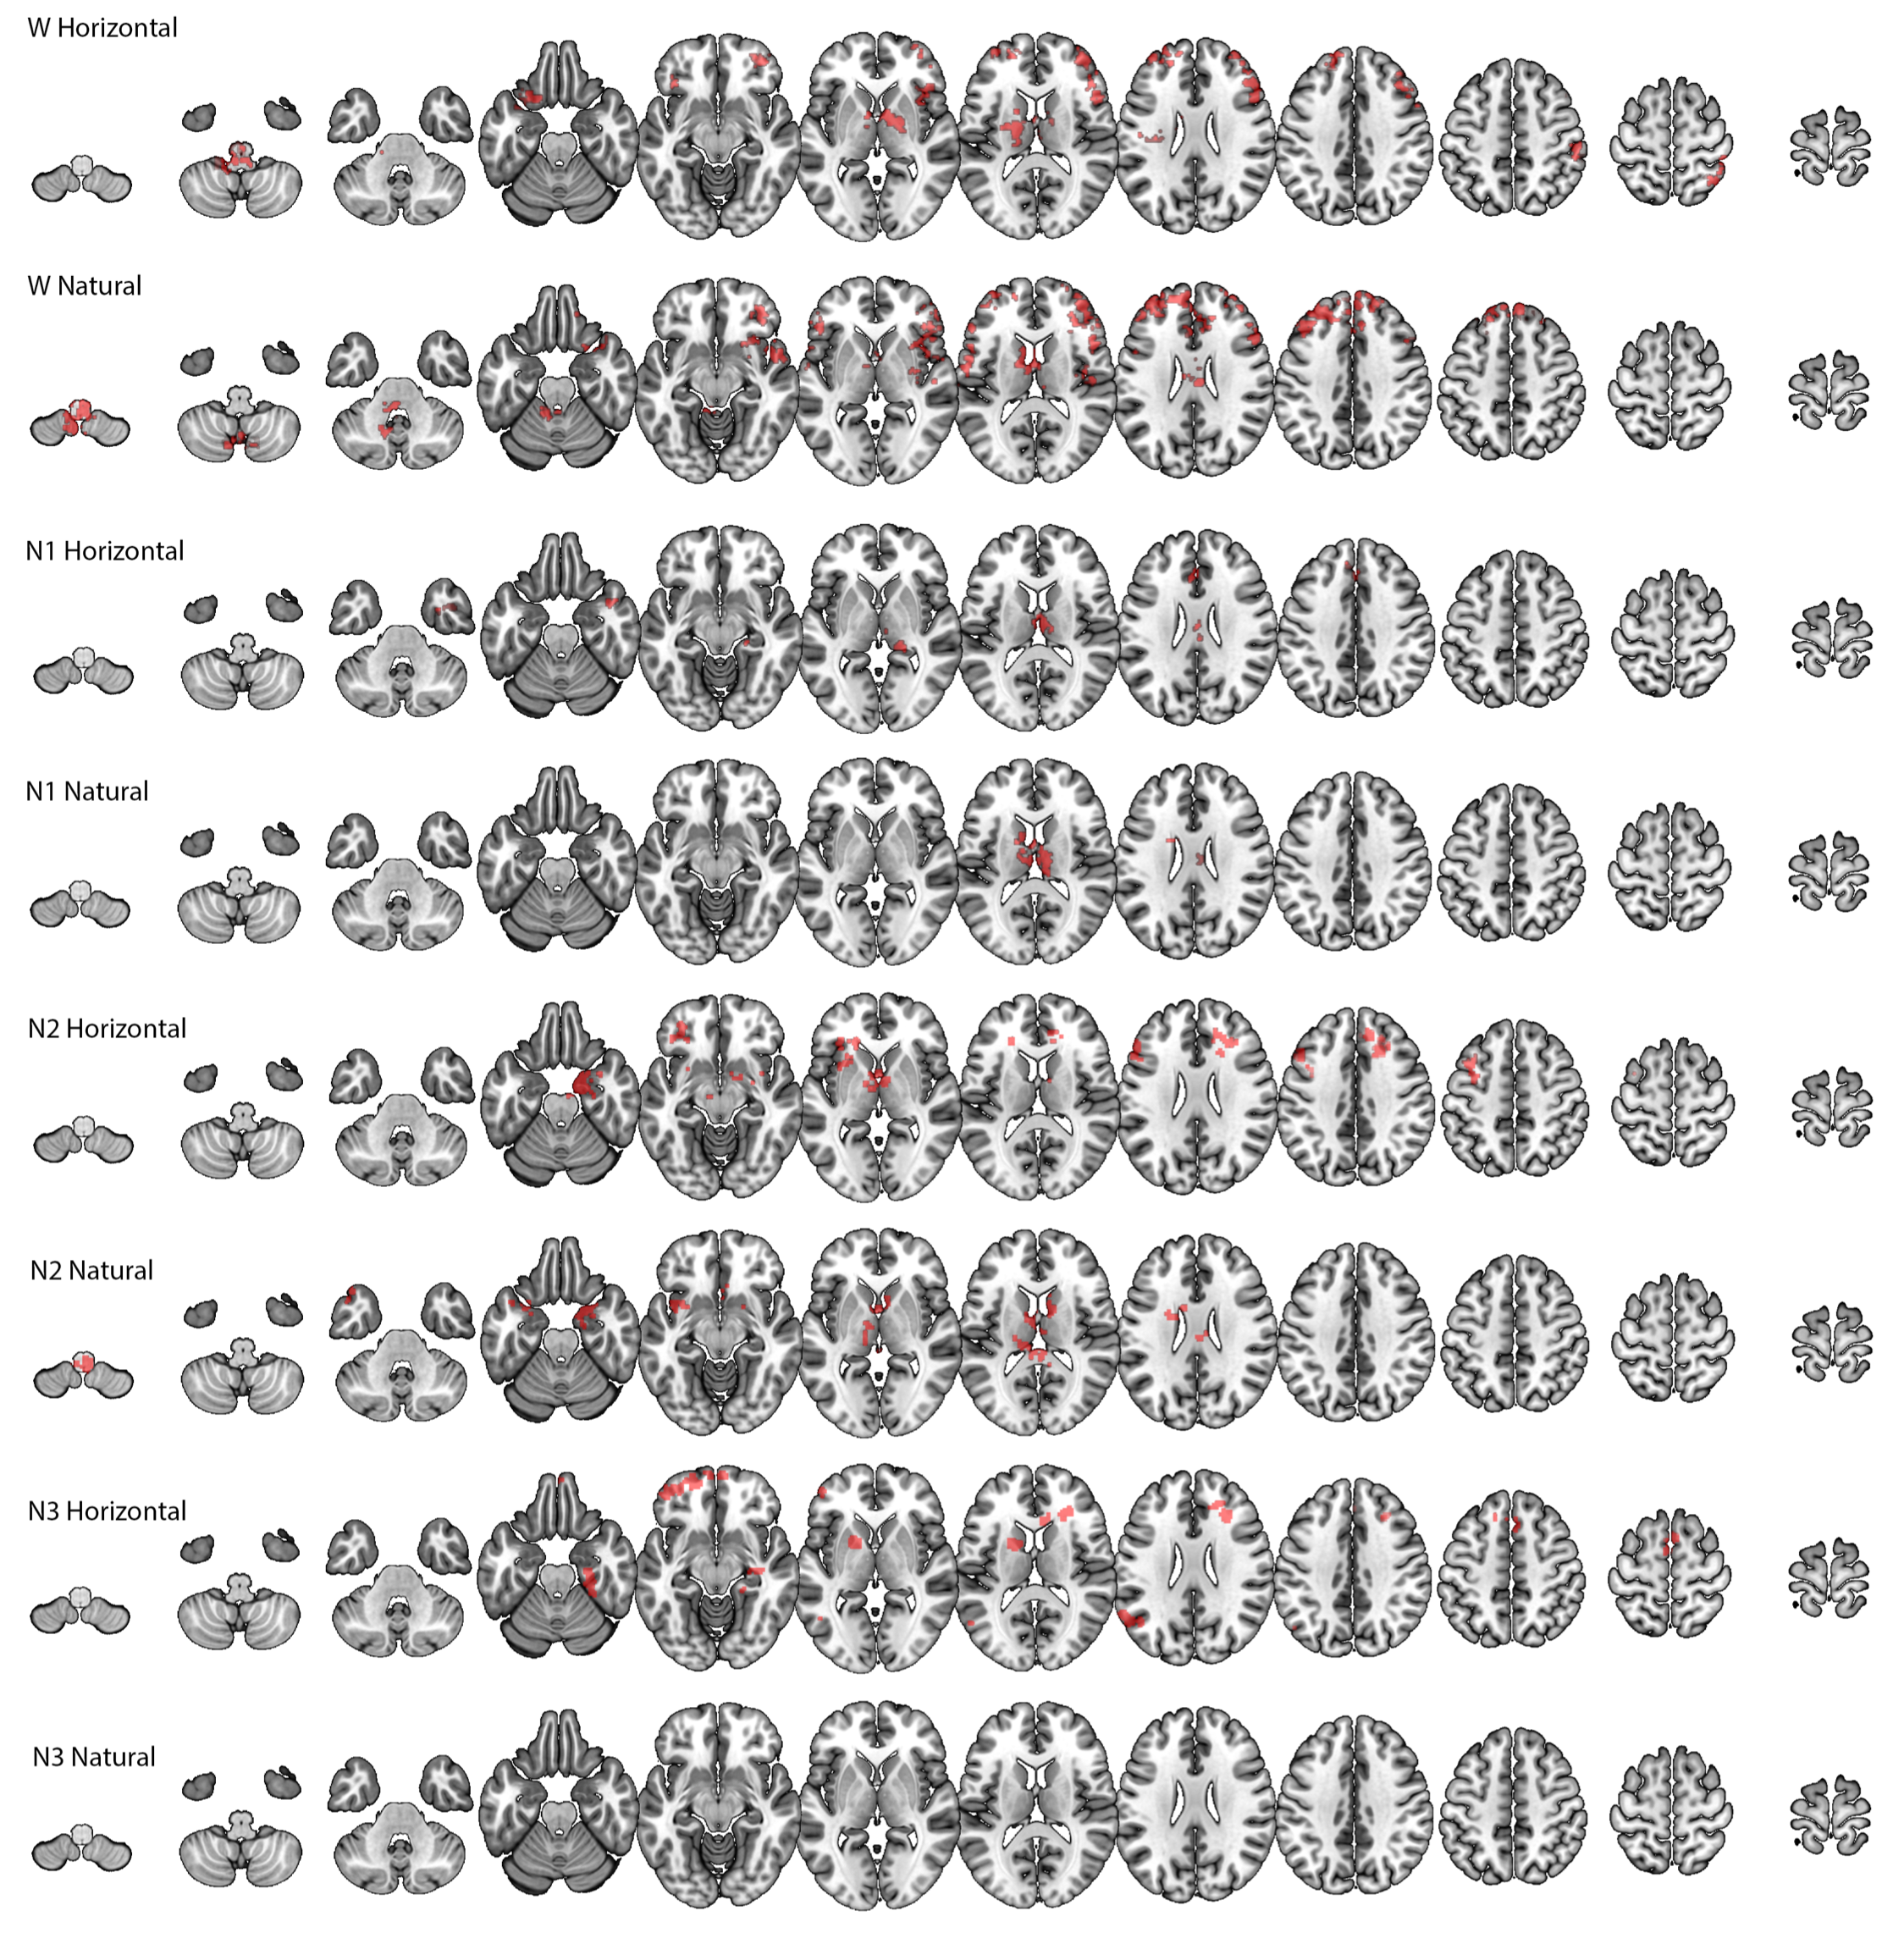

Single-voxel calculations, and group-level analyses. The sleep-staging procedure allowed us to obtain fMRI time series for wakefulness (W) and three different sleep stages: N1, N2 and N3. On the single participant level, for each of the four conditions, we conducted voxel-wise analyses to derive the node-degree histograms for the top and bottom graphs (i.e. these were derived for each voxel). These were represented as the empirical cumulative distribution function. With these CDFs we could answer the following two questions:

On the group level, to evaluate voxels showing statistically-significant AoVH within each study condition (W, N1, N2, N3) we conducted voxel-wise repeated measures ANOVA with two fixed factors; Time series view (two levels [Top, Bot]), and node-degree-histogram Bin (8 levels as explained above). To enable inferences about the population, we modeled participants as a random factor. In order to compare between any two conditions (e.g., W vs. N1) we derived the AoVH for each condition, and conducted a repeated measures ANOVA with 2 fixed factors: Condition (e.g., W vs. N1) and Node degree histogram bin of the difference histogram (8 bins, values 2(min)-9(max)). We note that 8 bins are used here, as the 9th bin would not be independent of the prior 8 (due to normalization).

These analyses returned a statistical significance value for the interaction term, for each brain voxel. We then implemented a clustering procedure forman99 to identify brain areas where many contiguous voxels, each with a value of .001 show a significant interaction: this identifies an ‘activation cluster’.

IV.1 Application to fMRI

We first compared the top and bottom visibility graphs within the Wakefulness and the three sleep stages (N1, N2 and N3). As shown in Figure 5, we found significant differences, predominantly in thalamic and frontal regions, for each of these conditions, with the exception of the case of VG in the N3 sleep condition.

To better understand these results, we determined which visibility values tended to contribute most strongly to the statistically-significant differences in degree distributions that produced the Wakefulness (W) results in Figure 5 (rows 1, 2). To this end, for each cluster we derived a histogram that communicated the visibility bins that most strongly differentiated the top and down degree distributions for each voxel in the cluster. We did this by (i) transforming the cluster to original space, (ii) for each voxel, identifying the bin that maximally differentiated the top from down histogram, (iii) transforming that value to common space, (iv) creating an average across participants for each voxel in the cluster. The resulting histograms communicated a very clear and consistent result: for VG the modal degree value that maximally differentiated the top and bottom histograms was 4, with narrow tails towards the values of 3 and 5 (indicating that for some participants, some voxels maximally differentiated the histograms at values 3 and 5). Importantly, there were no cases with means below 3 or above 5. For HVGs, in all clusters the modal degree value that maximally differentiated the top and bottom histograms was 3, with very narrow tails towards 2 and 4.

These findings are very important as they show that the differences identified by VGA (AoVH) were driven by very local dynamics rather than due to differences in propensity of isolated extreme events.

In a separate analysis, we also found that VGA profiles could discriminate wakefulness from sleep. As shown in Fig.6, we identified numerous areas, in both occipital (visual cortex) and lateral temporal cortices, where dynamics during wakefulness and N2 sleep differed significantly. No differences were found between W and N1 or between W and N3.

In applying this method, we first found that it offered a new view into spontaneous resting state dynamics in the human brain. While prior neuroimaging work based on amplitude-variance-asymmetry had pointed to sensory cortices as ones having different peak vs. pit dynamics AVA , the current results identify frontal regions as exhibiting asymmetric resting-state BOLD fluctuations during wakeful rest. Furthermore, these asymmetric patterns were also found during the deeper sleep stages (N2 and N3), which is a departure from prior findings (DAVIS16) where AVA failed to identify such signatures. An important result was that in all clusters, these dynamics were driven by differences in the relative frequency of time points (nodes) with relatively low degree, indicating that these differences are not due to a difference in relative frequency of rare, extreme events but due to differences in frequency of time points with relatively moderate connectivity – i.e., a very local phenomenon.